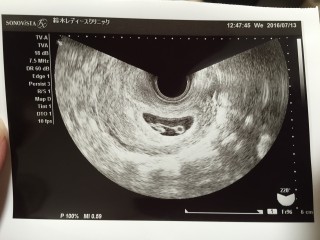

体外受精(凍結胚移植5日目胚盤胞)で授かりました。 D28/BT10妊娠判定hCG691。 5w5d胎嚢確認GS16.7mm。 7w2d心拍・心音確認CRL12.4mm。 たくましくドックンドックン動く心音を聞かせてもらって感動しました。 母子手帳も貰い8w2dにクリニック卒業です。